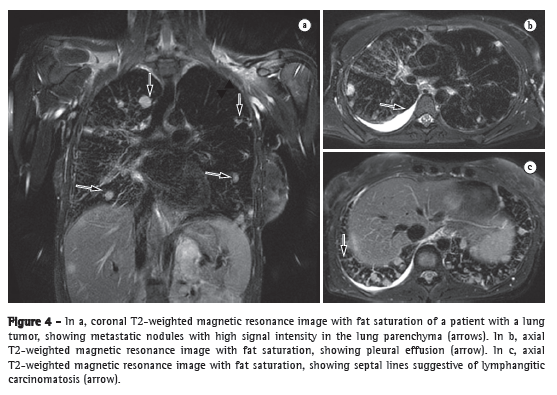

Magnetic resonance imaging

Advances in the techniques for acquiring and processing magnetic resonance imaging of the heart have allowed three-dimensional evaluation of the RV and detailed tomographic visualization of its morphology. Cardiac magnetic resonance imaging (CMRI) creates a clear distinction between the myocardium and intracavitary blood, presenting well-defined myocardial and endocardial borders.(8) Because the RV presents the aforementioned particularities and CMRI allows a more detailed visualization of the RV, CMRI is currently considered the gold standard for a noninvasive evaluation of the RV.(9,10) Studies in which CMRI was used to evaluate patients with PH showed that, when compared with control group patients, PH patients presented with a significant increase in end-systolic and end-diastolic volumes, as well as in right ventricular muscle mass, together with a significant reduction in right ventricular ejection fraction. Other studies have shown ventricular septal bowing, together with a reduction in the LV volume in early diastole, revealing impaired left ventricular function associated with right ventricular dysfunction.(11) One group of authors demonstrated that the position of the septum, as determined by calculating its shift toward the LV, was accurate in predicting right ventricular systolic pressure.(12) Even without the use of contrast enhancement, CMRI allows excellent visualization of the PA, and it is possible to assess PA compliance and flow by means of the phase-contrast technique. In patients with PH, PA compliance values are significantly lower.(13) One study showed that measurements of pulsatility (which is related to compliance) can also correlate with the response to the NO test.(14) The measurement of PA velocity and the time it takes to reach the maximum velocity (acceleration time) are reduced in patients with PH, and these measurements are related to systolic volume as measured by RHC.(15) In addition, CMRI plays a role in the follow-up of patients with PH. Two studies used CMRI before treatment initiation and 6-12 months after treatment initiation. In one of the studies, the patients received epoprostenol, and in the other, they received bosentan.(16,17) In both studies, improvement in the six-minute walk test (6MWT) was significantly related to improvement in right ventricular function parameters, as determined by CMRI. In another study, CMRI was used before and after pulmonary thromboendarterectomy.(18) The study showed a significant reduction in myocardial mass, right ventricular end-systolic volume, and right ventricular end-diastolic volume, as well as increased left ventricular volumes, reflecting the reversion of ventricular remodeling and septal deviation, hemodynamic improvement having been achieved with the surgical procedure (Figure 2c).

After the presence of PH and its correct hemodynamic classification are confirmed by RHC, various tests should be performed in order to determine the specific etiology of PH. It should be highlighted that idiopathic PH is a differential diagnosis, and it is fundamental to follow an appropriate flowchart to facilitate the diagnostic investigation (Figure 4).